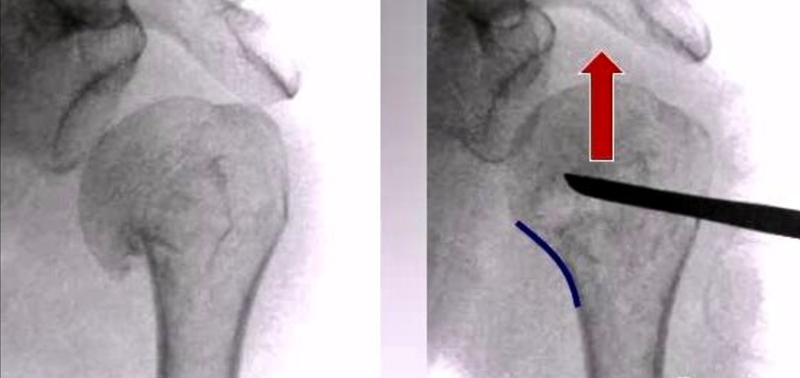

1、内翻压缩型二部分骨折闭合复位固定

(1)病理改变

肱骨干在内侧嵌插进入肱骨头,而外侧的骨膜完整,不会出现骨折分离。两个骨折块通常向前互相成角,完整的骨膜和骨折嵌插保留了一定的稳定性。

(2)复位固定技巧

肱骨干维持在轻度外展位轴向牵引,同时用大拇指在骨折部位成角处自前向后按压,以纠正骨折端向前成角。在复位过程中,必须确保两骨折端的内侧皮质尽可能的精确对位。

如果应用这种手法复位的方式不能将嵌插松解,则需要在骨折端下方5cm处纵形切一小口,置入一把骨膜起子,起子从肱骨干前方放入,紧贴皮质滑行,到达内侧肱骨骨皮质骨折端,维持上肢轻度外展并牵引,用起子将肱骨头翘起。

一旦完成以上步骤,在维持复位状态下,助手沿着预先已设定好的线路打入2.0mm克氏针2-3枚,即从骨折端以远打入直到针尖位于肱骨头的软骨下骨。

2、内翻分离型二部分骨折

表现为肱骨头和干的完全分离,预示着“骨膜桥”的损毁,因此成为极其不稳定的骨折。由于冈上肌的牵拉肱骨头发生旋转呈内翻位,而骨折远端的肱骨干受胸大肌的牵拉向前内移位。

(2)闭合复位固定技巧

术者一只手对肱骨干进行持续的牵引,另一只手位于骨折端下方,紧扣肱骨干,施加向外侧和背侧的力(外牵后推),抵消胸大肌的牵拉力量,直到两骨折块在正确的轴线上相接触。

接下来,在肩峰下区域上方的前内1/3处做一小切口,用大布巾钳尖部在肩胛上肌腱附着点处固定大结节。然后向下向后向内牵引,抵消来自肩胛上肌腱的牵拉力量,使得肱骨头从内翻位旋转回到中立位。一旦完成,将事先准备好的两枚2.0mm克氏针打入,针尖到达肱骨头软骨下骨。